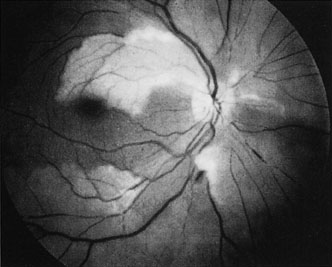

Cilioretinal arteries can be selectively obstructed (Fig. 3). More commonly, however, they occur in association with central retinal vein obstruction.113 When they supply a significant portion of the macula, decreased visual acuity is common. Prognosis for visual outcome in such patients is good. Brown and co-workers114 studied 10 eyes having an isolated cilioretinal artery obstruction. Of those, 60% had an initial visual acuity of 20/40 or better and on follow-up examination, all eyes but one had a best-corrected visual acuity of 20/40 or better.114